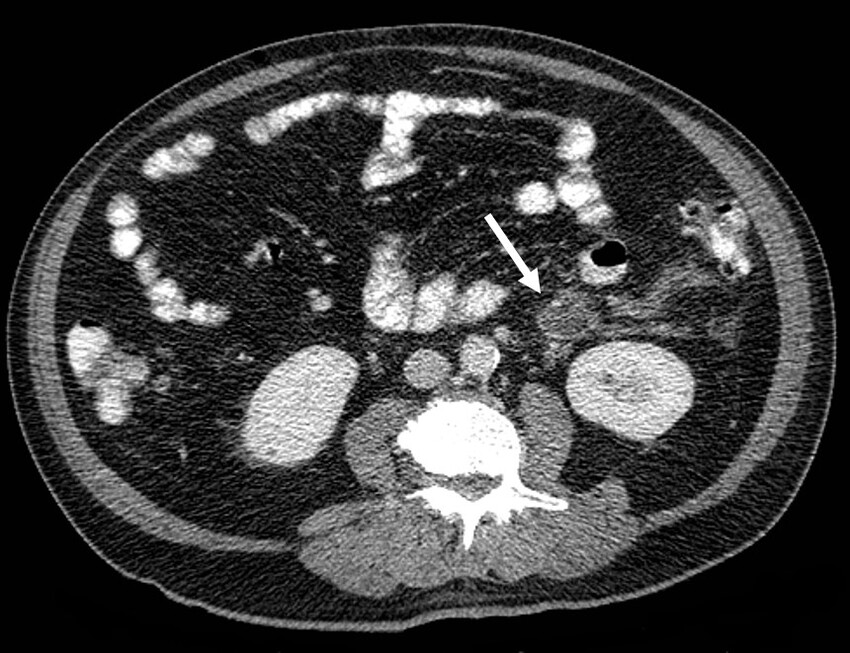

Además, se identificó trombosis de la vena mesentérica inferior y sus afluentes, la vena cólica izquierda y vena rectal superior, con marcado aumento en su calibre, engrosamiento e irregularidad de sus paredes, además de estriación de la grasa circundante, hallazgos compatibles con tromboflebitis (Figs. 2, 3 y 4).